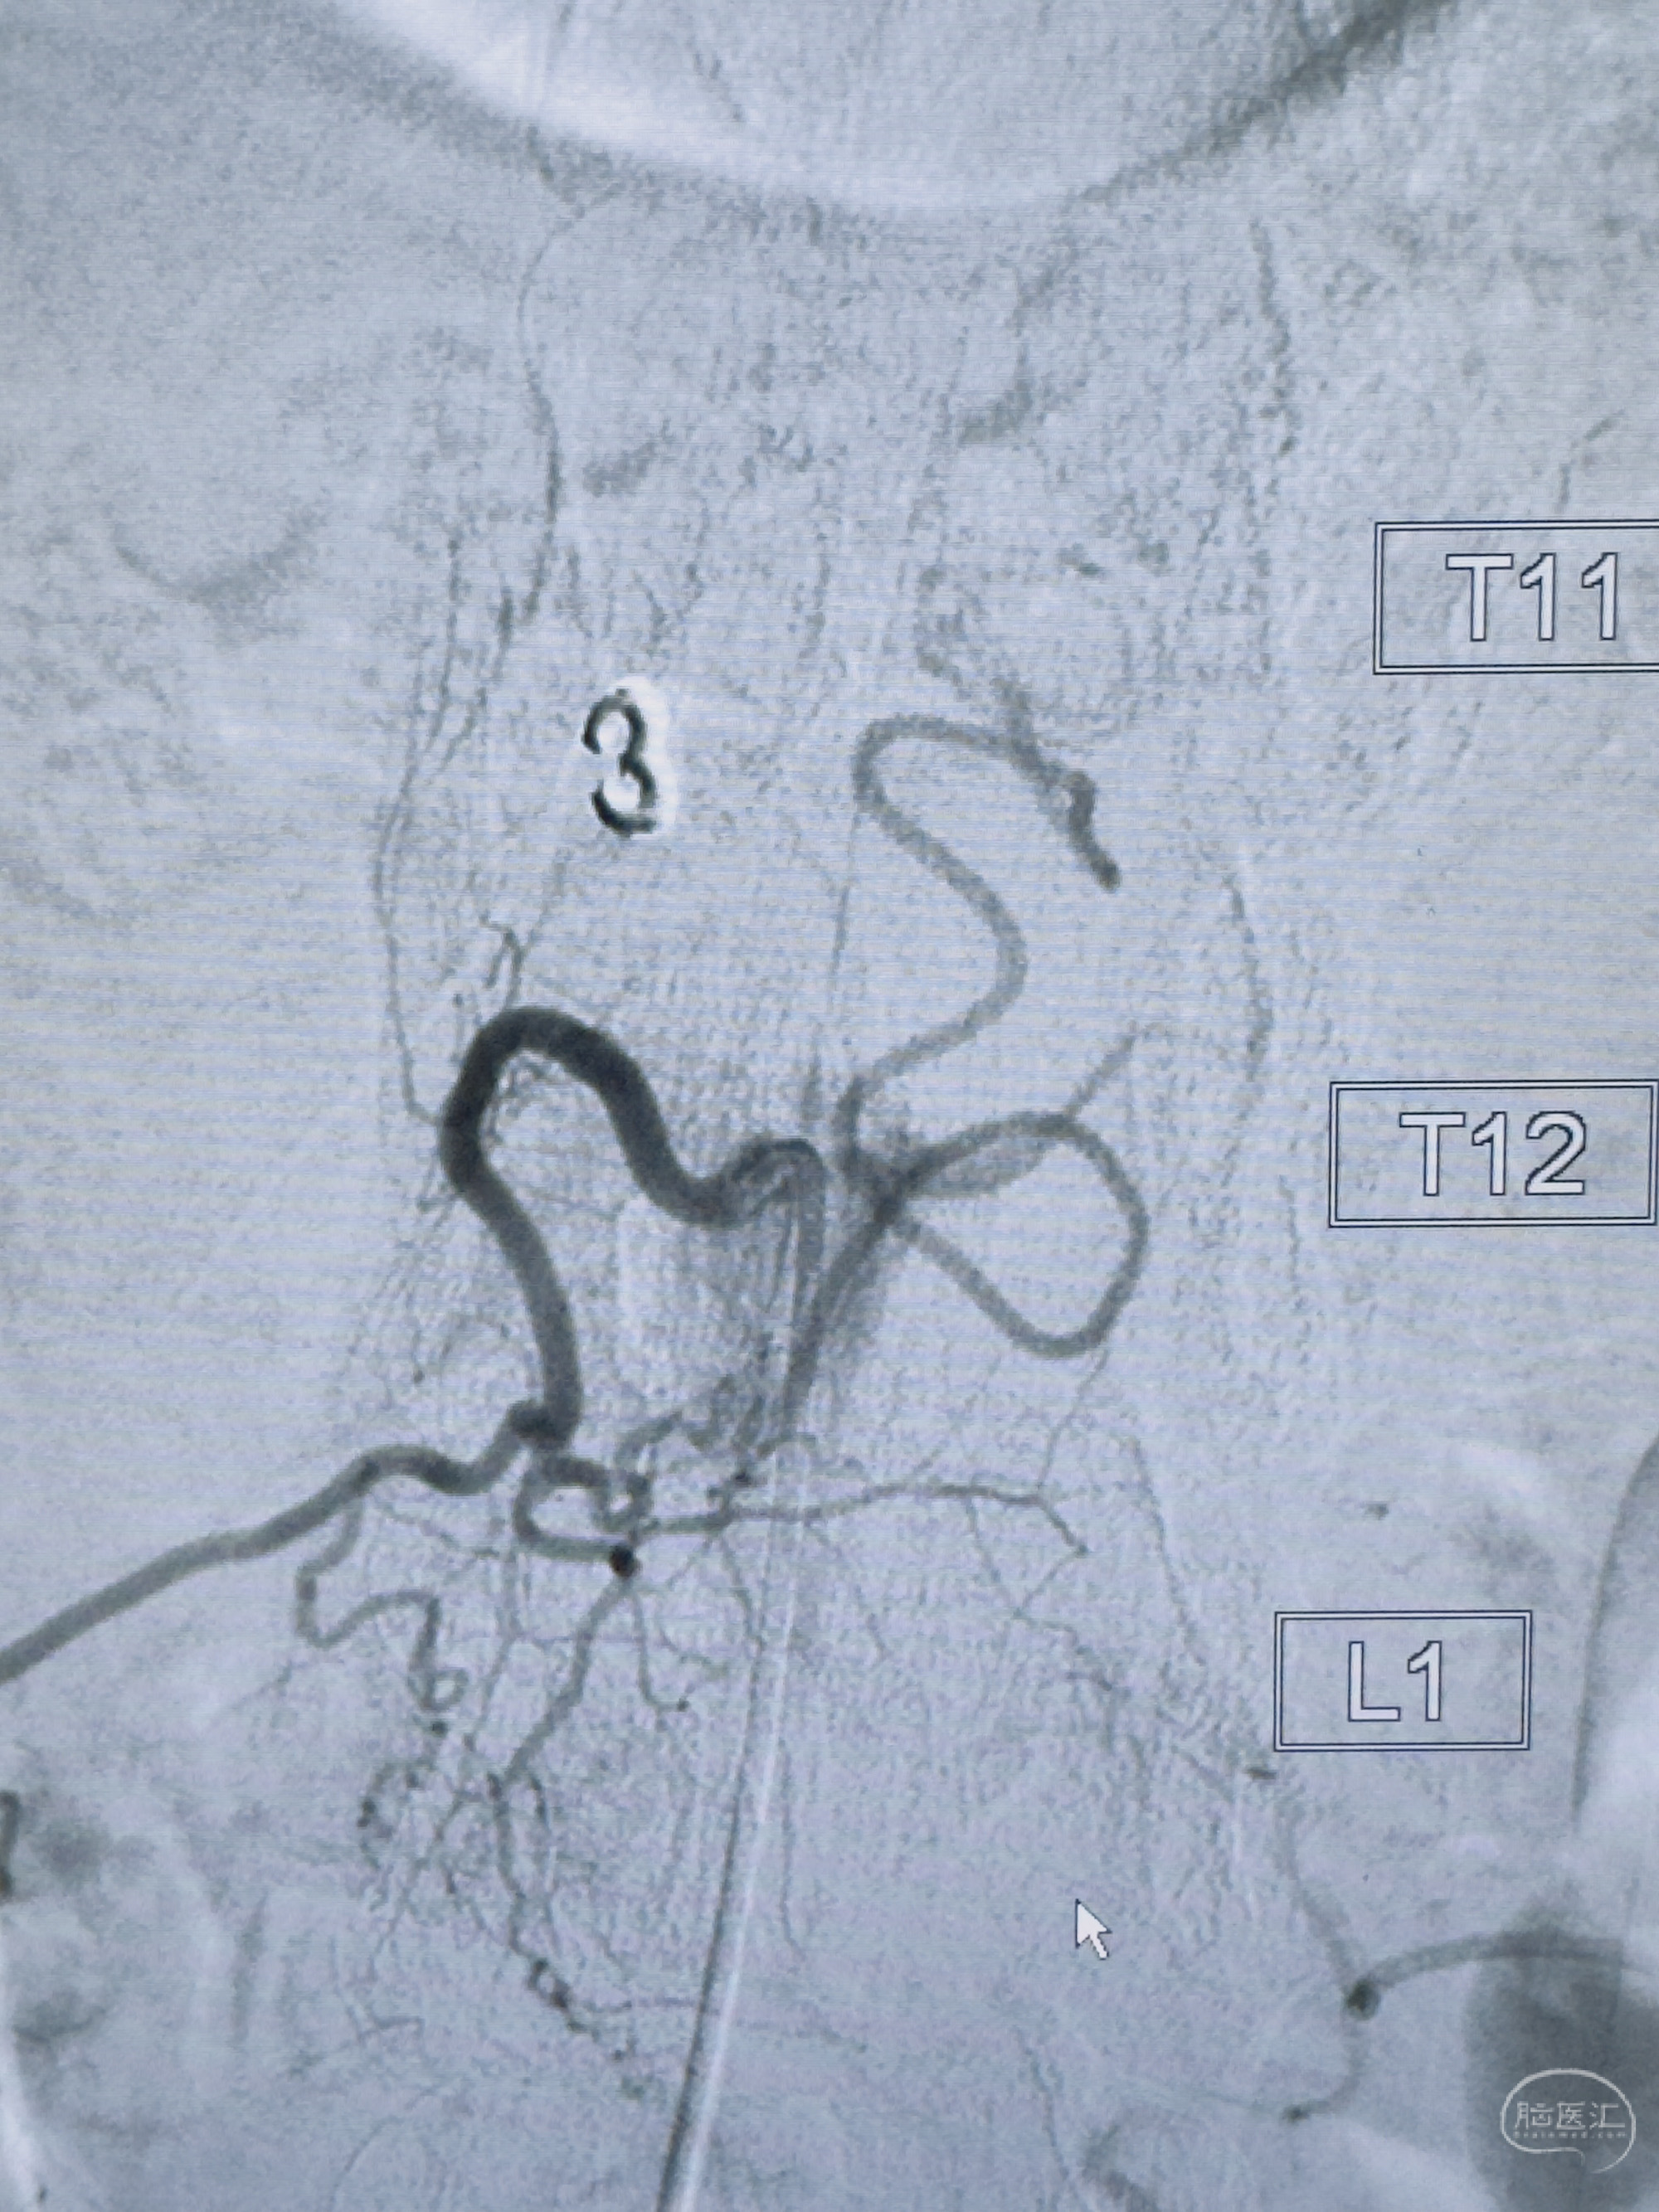

2023-10-13DSA:右侧L1水平硬脊膜动静脉瘘,供血动脉为右侧L1,附近动脉未见明确吻合供血,供血动脉处可见脊髓前动脉发出